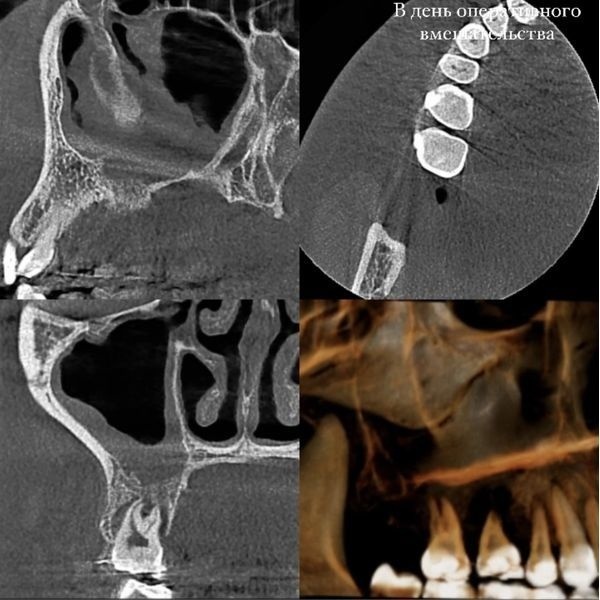

- удалили зуб 1.6;

- очистили лунку от инфицированных тканей и пломбировочного материала, пока не достигли здоровой кости, и подготовили её под аутотрансплантат — другой зуб девушки;

- закрыли отверстие между полостью рта и гайморовой пазухой с помощью A-PRF сгустка, полученного из собственной крови пациентки;

- удалили зуб мудрости (зуб 1.8), поместили его в подготовленное ложе, повернули таким образом, чтобы он соответствовал анатомии лунки зуба 1.6, и дополнительно зафиксировали;

- обработали реимплантированный зуб так, чтобы он временно не участвовал в жевании, после чего наложили швы и обездвижили его ортодонтическим ретейнером.

Стоит отметить, что зуб 1.8 не только заменил удалённый моляр, но и помог закрыть сообщение между полостью рта и гайморовой пазухой.